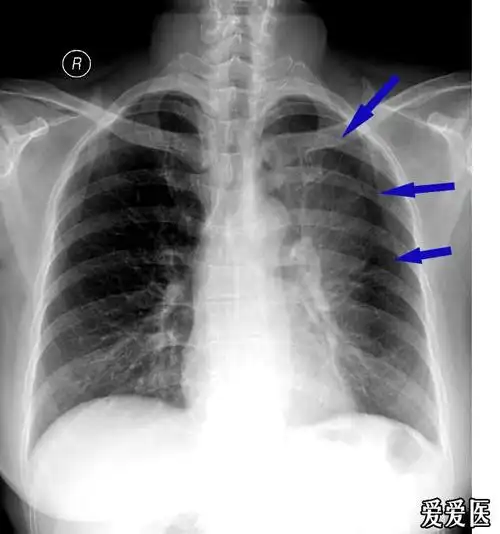

发张典型的左肺上叶不张的图片,大家看下哈 - 医学影像学讨论版 - 爱